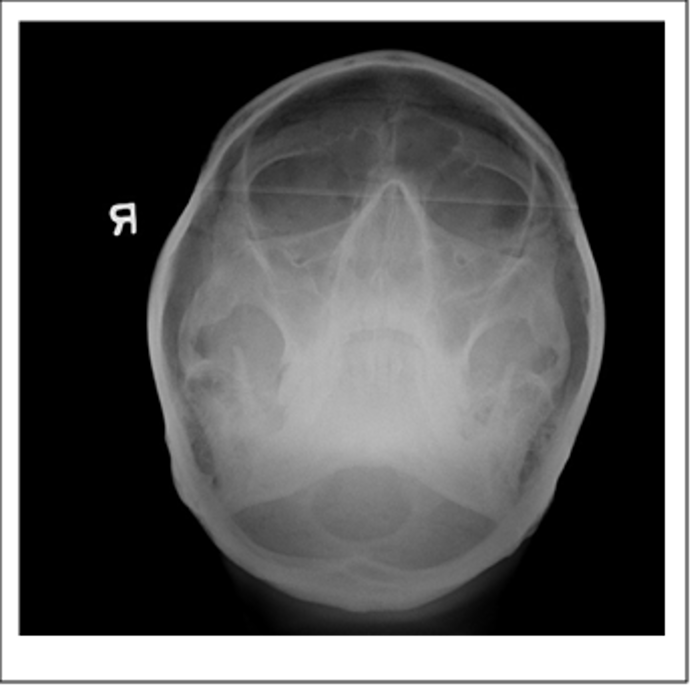

Submentovertical of the cranial base - Schuller method

Submentovertical of cranial base - Schuller method